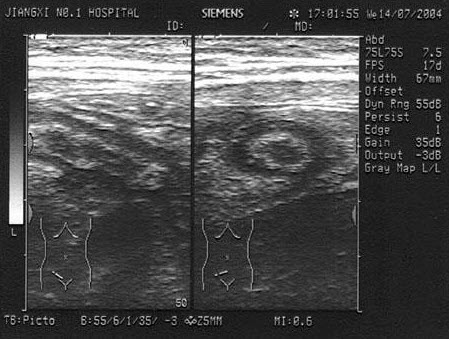

65、单项选择题

结合超声图像,该病例肾结石为哪一部位()

A.下极肾盏

B.中极肾盏

C.上极肾盏

D.肾门

E.肾乳头处